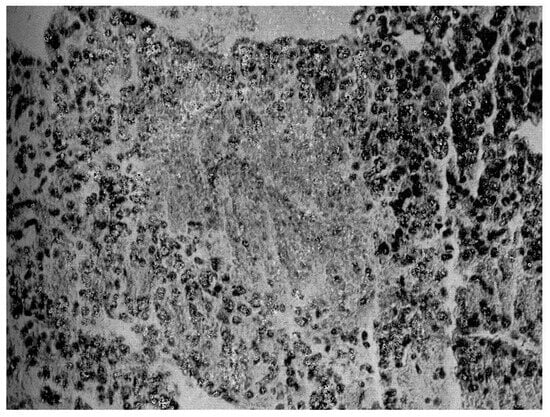

Instead, when transferred to the Surgical Semeiotics Unit for surgery, the surgeon, during the laparotomy, found a large 305 gr mass attached to the superior pole of the adrenal gland, which was removed and histopathologically verified as adrenocortical carcinoma (Figure 3).

Figure 3. Histopathological findings on surgical specimen: widespread subversion of glandular architecture with high nuclear grade, high mitotic grade, atypical mitoses, and vascular and capsule invasion supporting the diagnosis of adrenocortical carcinoma, also along the lines indicated by the more recent WHO overview [1,5].